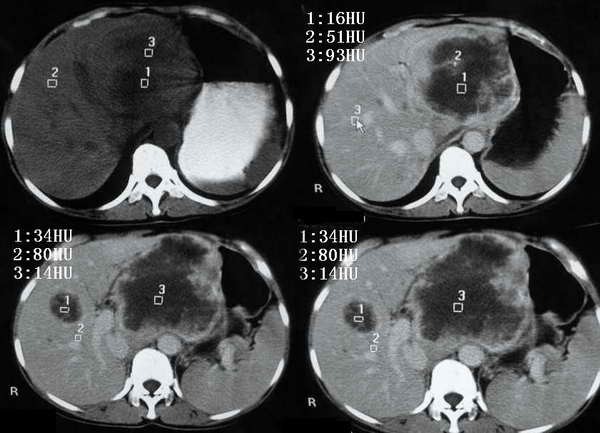

以下是引用东北在2006-1-20 15:36:00的发言:[br]图象少 外生性肝癌并肝内转移侵犯胃窦[br]胰腺的图象少

以下是引用wangqj1976在2006-1-20 21:11:00的发言:[br]不支持胰腺癌的诊断[br]1位置抬高,病变在腹腔干之上, 2胆管、胆囊主胰管不扩张,化验胆红素不高。[br]不支持肝癌[br]1无乙肝、肝硬化病史2病变强化方式[br]支持胃癌可能性大,合并肝转移、胰腺受累。(病人还贫血)[br]脾大,可以用肿瘤压迫脾静脉来解释。[br]建议做上消化道钡餐检查。